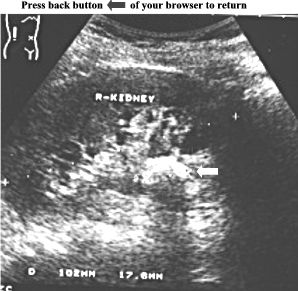

Ultrasound

examination

of

this

normal

sized

right

kidney

revealed

an

hyperechoic

area

in

the

vicinity

renal

hilum

(see

arrow).

size

was

1,8cm

and

a

posterior

acoustic

shadowing

demonstrated.

ANSWER:

stone

pelvis.